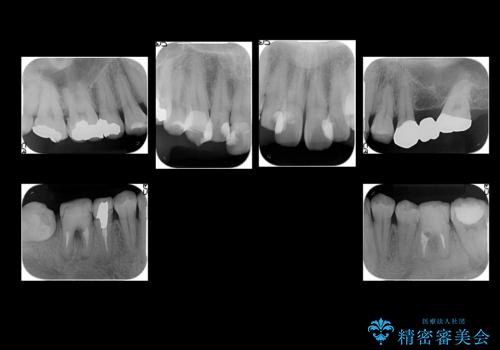

- 短期間で歯並びを治したいとのこと。期間が短ければセラミックでかぶせる治療できれいにするのでも構わない。虫歯の治療もすべてお願いしたいとのことでした。

右下の奥歯は残せない可能性を説明しました。

また、歯並びの矯正をするのではなければ、右上の八重歯は、犬歯を抜くか、奥に入っている歯を抜くかになるとお伝えしました。結果、根の長い犬歯を残して右上の前歯を抜歯しブリッジにしました。また、前歯の神経は極力取らないで治療を行いました。(結果神経を取る治療は前歯には行っておりません)

右下奥歯二本はインプラントにしました。(横浜桜木町歯科院長 大元先生による)